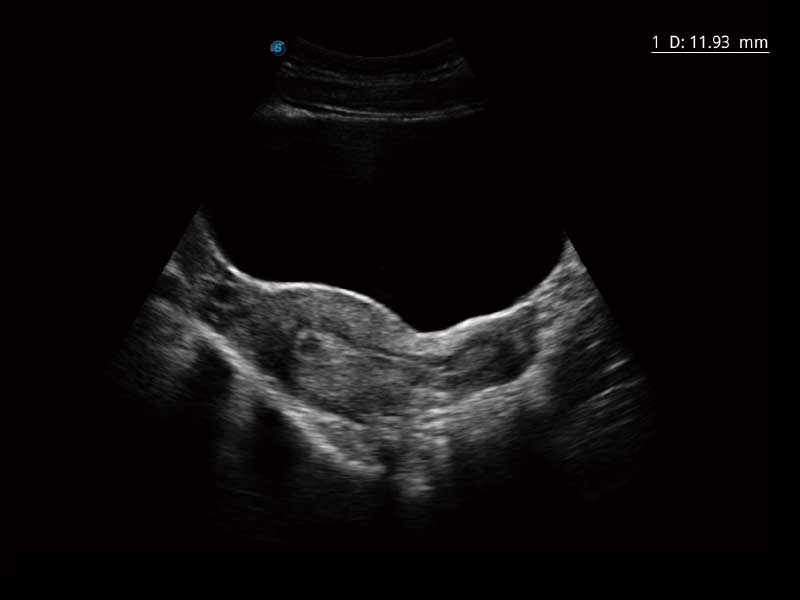

μ-Scan微米成像、空间复合成像、高分辨率血流成像。

单键操作,可快速优化多个二维及多普勒图像参数,获得优异图像效果。